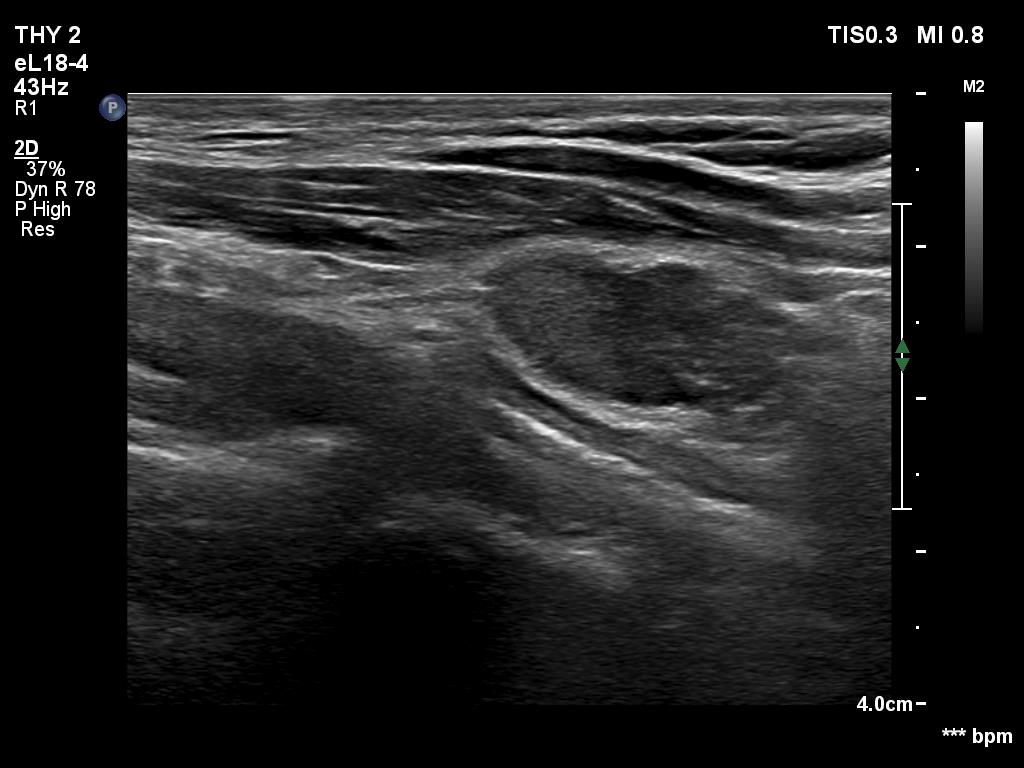

First examination (1st to third rows of images):

Clinical data: A 14-year-old boy was referred for evaluation of a nodule discovered by himself.

Palpation: a hard, not freely moveable nodule in the isthmic part of the left lobe.

Hormonal examination: indicated euthyroidism with TSH 2.09 mIU/L.

Ultrasonography revealed a hypoechogenic nodule in the ventromedial part of the left lobe. The nodule had irregular borders, contained microcalcifications and displayed perinodular and irregular intranodular blood flow.

Cytology: follicular tumor.

Based on the ultrasound and cytological pattern combined, the probability of cancer was greater than the average.

Histopathology disclosed an embryonal-type follicular adenoma in the left lobe. Almost the entire lobe was consisted of the adenoma. There were within the nodule large fields of lymphocytic infiltration. In the middle portion of the nodule a papillary carcinoma was found with a maximal diameter of 15 mm with metastasis to 3 of the removed 9 lymph nodes in the left side of the neck.